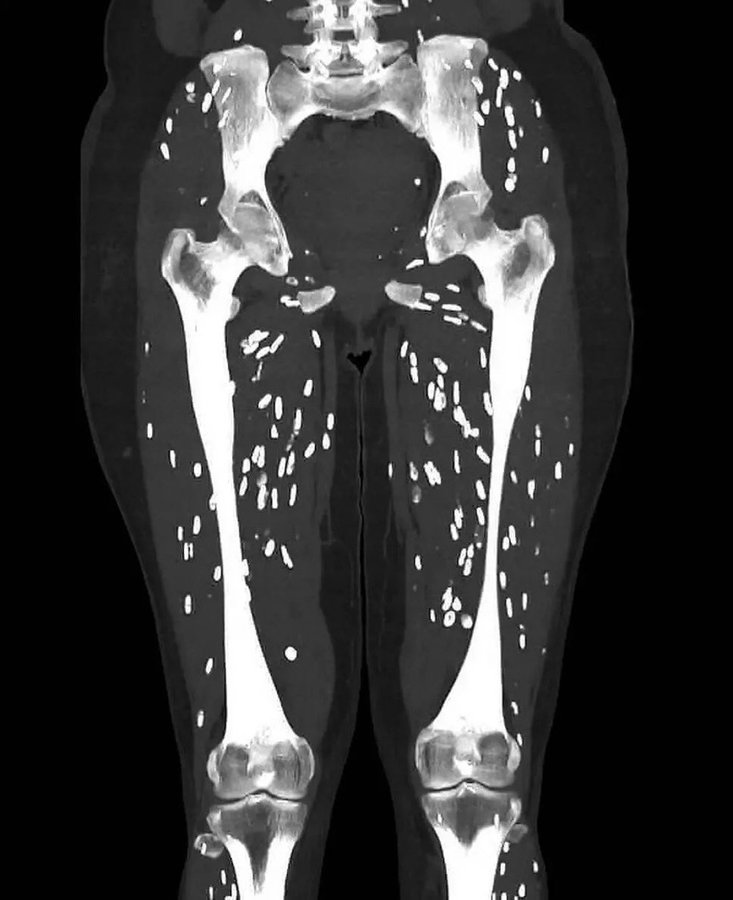

യൂണിവേഴ്സിറ്റി ഓഫ് ഫ്ലോറിഡ ഹെൽത്ത് ജാക്സൺവില്ലെയിലെ എമർജൻസി റൂം ഫിസിഷ്യനായ ഡോ. സാം ഗാലി തൻ്റെ എക്സ് അക്കൗണ്ടിൽ ഞെട്ടിക്കുന്ന ഒരു ചിത്രം പോസ്റ്റ് ചെയ്തു, “ഞാൻ കണ്ടിട്ടുള്ളതിൽ വച്ച് ഏറ്റവും ഭ്രാന്തമായ സിടി സ്കാനുകളിൽ ഒന്ന്” എന്നാണ് ഇതിനെ വിശേഷിപ്പിച്ചത്. രോഗിയുടെ കാലുകൾ പേശികളെ കടന്നാക്രമിച്ച ഒരു പരാന്നഭോജി അണുബാധയുടെ പിടിയിലാണെന്ന് സ്കാൻ കാണിച്ചു.

Here’s one of the craziest CT scans I’ve ever seen

What’s the diagnosis? pic.twitter.com/DSJmPfCy9L

അണുബാധ സാധാരണയായി സിടി സ്കാനുകളിൽ വെളുത്ത പാടുകളായി കാണപ്പെടുന്നു, പലപ്പോഴും “അരി ധാന്യം കാൽസിഫിക്കേഷൻ” എന്ന് വിളിക്കപ്പെടുന്നു. 5-12 ആഴ്ചയ്ക്കുള്ളിൽ, വിഴുങ്ങിയ സിസ്റ്റുകൾ പ്രായപൂർത്തിയായ ടേപ്പ്വേമുകളായി വികസിക്കുമെന്ന് ഡോ ഘാലി അഭിപ്രായപ്പെട്ടു. “അതിനാൽ ഇവിടുത്തെ കഥയുടെ ധാർമ്മികത, വൃത്തിയായി സൂക്ഷിക്കാനും എപ്പോഴും കൈ കഴുകാനും, ഒരിക്കലും അസംസ്കൃതമായതോ വേവിക്കാത്തതോ ആയ പന്നിയിറച്ചി കഴിക്കാതിരിക്കാൻ പരമാവധി ശ്രമിക്കുക എന്നതാണ്,” അദ്ദേഹം കൂട്ടിച്ചേർത്തു.